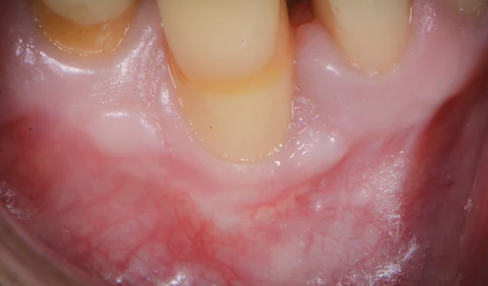

2. 잇몸 퇴축 증상 – 이런 변화가 보이면 의심하세요

잇몸 퇴축은 서서히 진행되기 때문에 자각하기 어려운 경우가 많지만, 다음과 같은 증상이 나타난다면 반드시 치과 검진이 필요합니다.

- 치아가 예전보다 더 길어 보임

- 찬물, 찬바람에 이가 시림

- 양치질할 때 잇몸에서 피가 남

- 치아 사이 틈이 벌어지고 음식물 끼임

- 잇몸 선이 불규칙하거나 쪼그라든 형태

- 입냄새(구취) 또는 잇몸 통증

치은퇴축은 심할 경우 치아를 지지하는 치조골까지 손상시켜 결국 치아가 흔들리거나 빠질 수 있습니다.